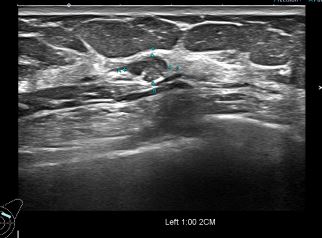

상기환자 외부검사이상으로 정밀검사 권유받아 내원하신 60대 여성분으로

좌측유방 혹 총조직검사 시행해 유방암 진단되었습니다.